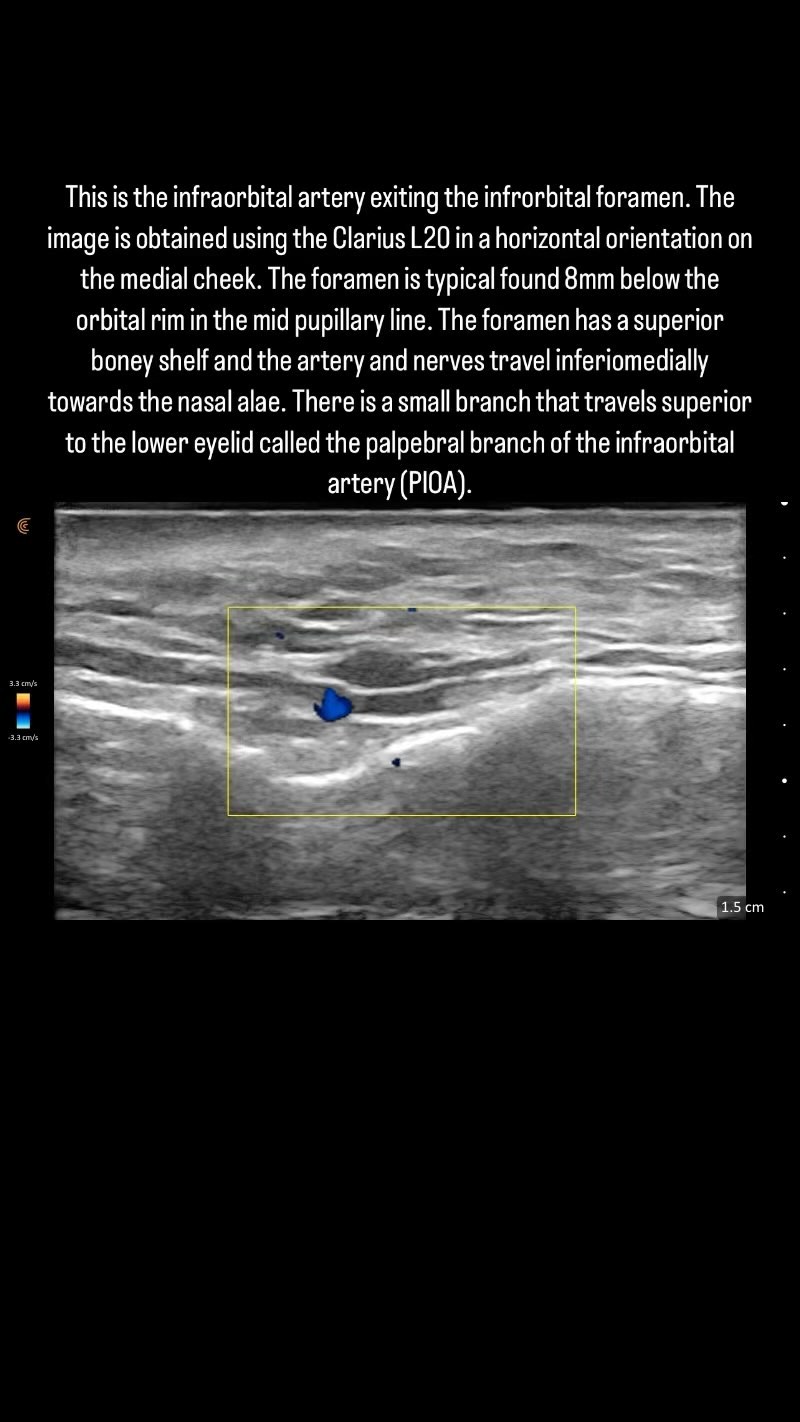

This is the infraorbital artery exiting the infrorbital foramen. The image is obtained using the Clarius L20 in a horizontal orientation on the medial cheek. The foramen is typical found 8mm below the orbital rim in the mid pupillary line. The foramen has a superior boney shelf and the artery and nerves travel inferiomedially towards the nasal alae. There is a small branch that travels superior to the lower eyelid called the palpebral branch of the infraorbital artery (PIOA).